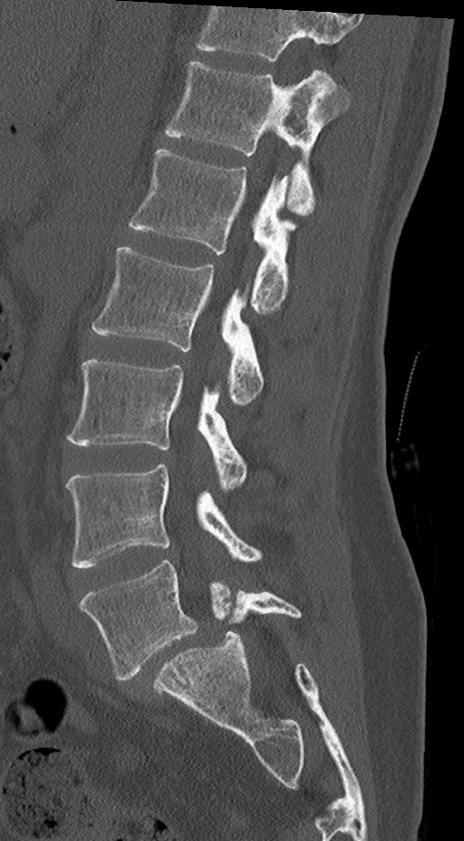

【整形】TIPS症例4 腰椎CT(矢状断像)

腰椎CT